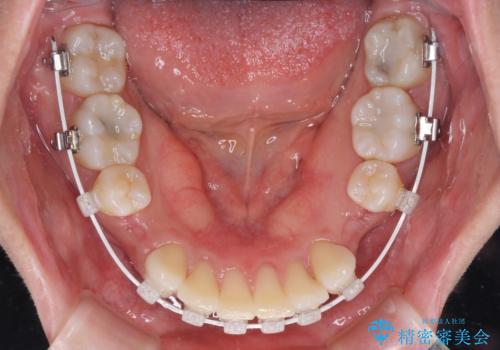

奥歯の咬み合わせ改善が必要なため、ワイヤー装置による矯正治療を強くお勧めしまたが、本人の希望でインビザラインにて治療を開始することとなりました。

インビザラインでの抜歯治療は予定通りに治療が進まないことが多いため、必要であればワイヤー矯正に切り替えるとお伝えした上で治療を開始しました。

2年ほどインビザラインを使用しましたが、どうしても歯の移動がマウスピースに追随せず、全顎ワイヤー矯正へ切り替えました。